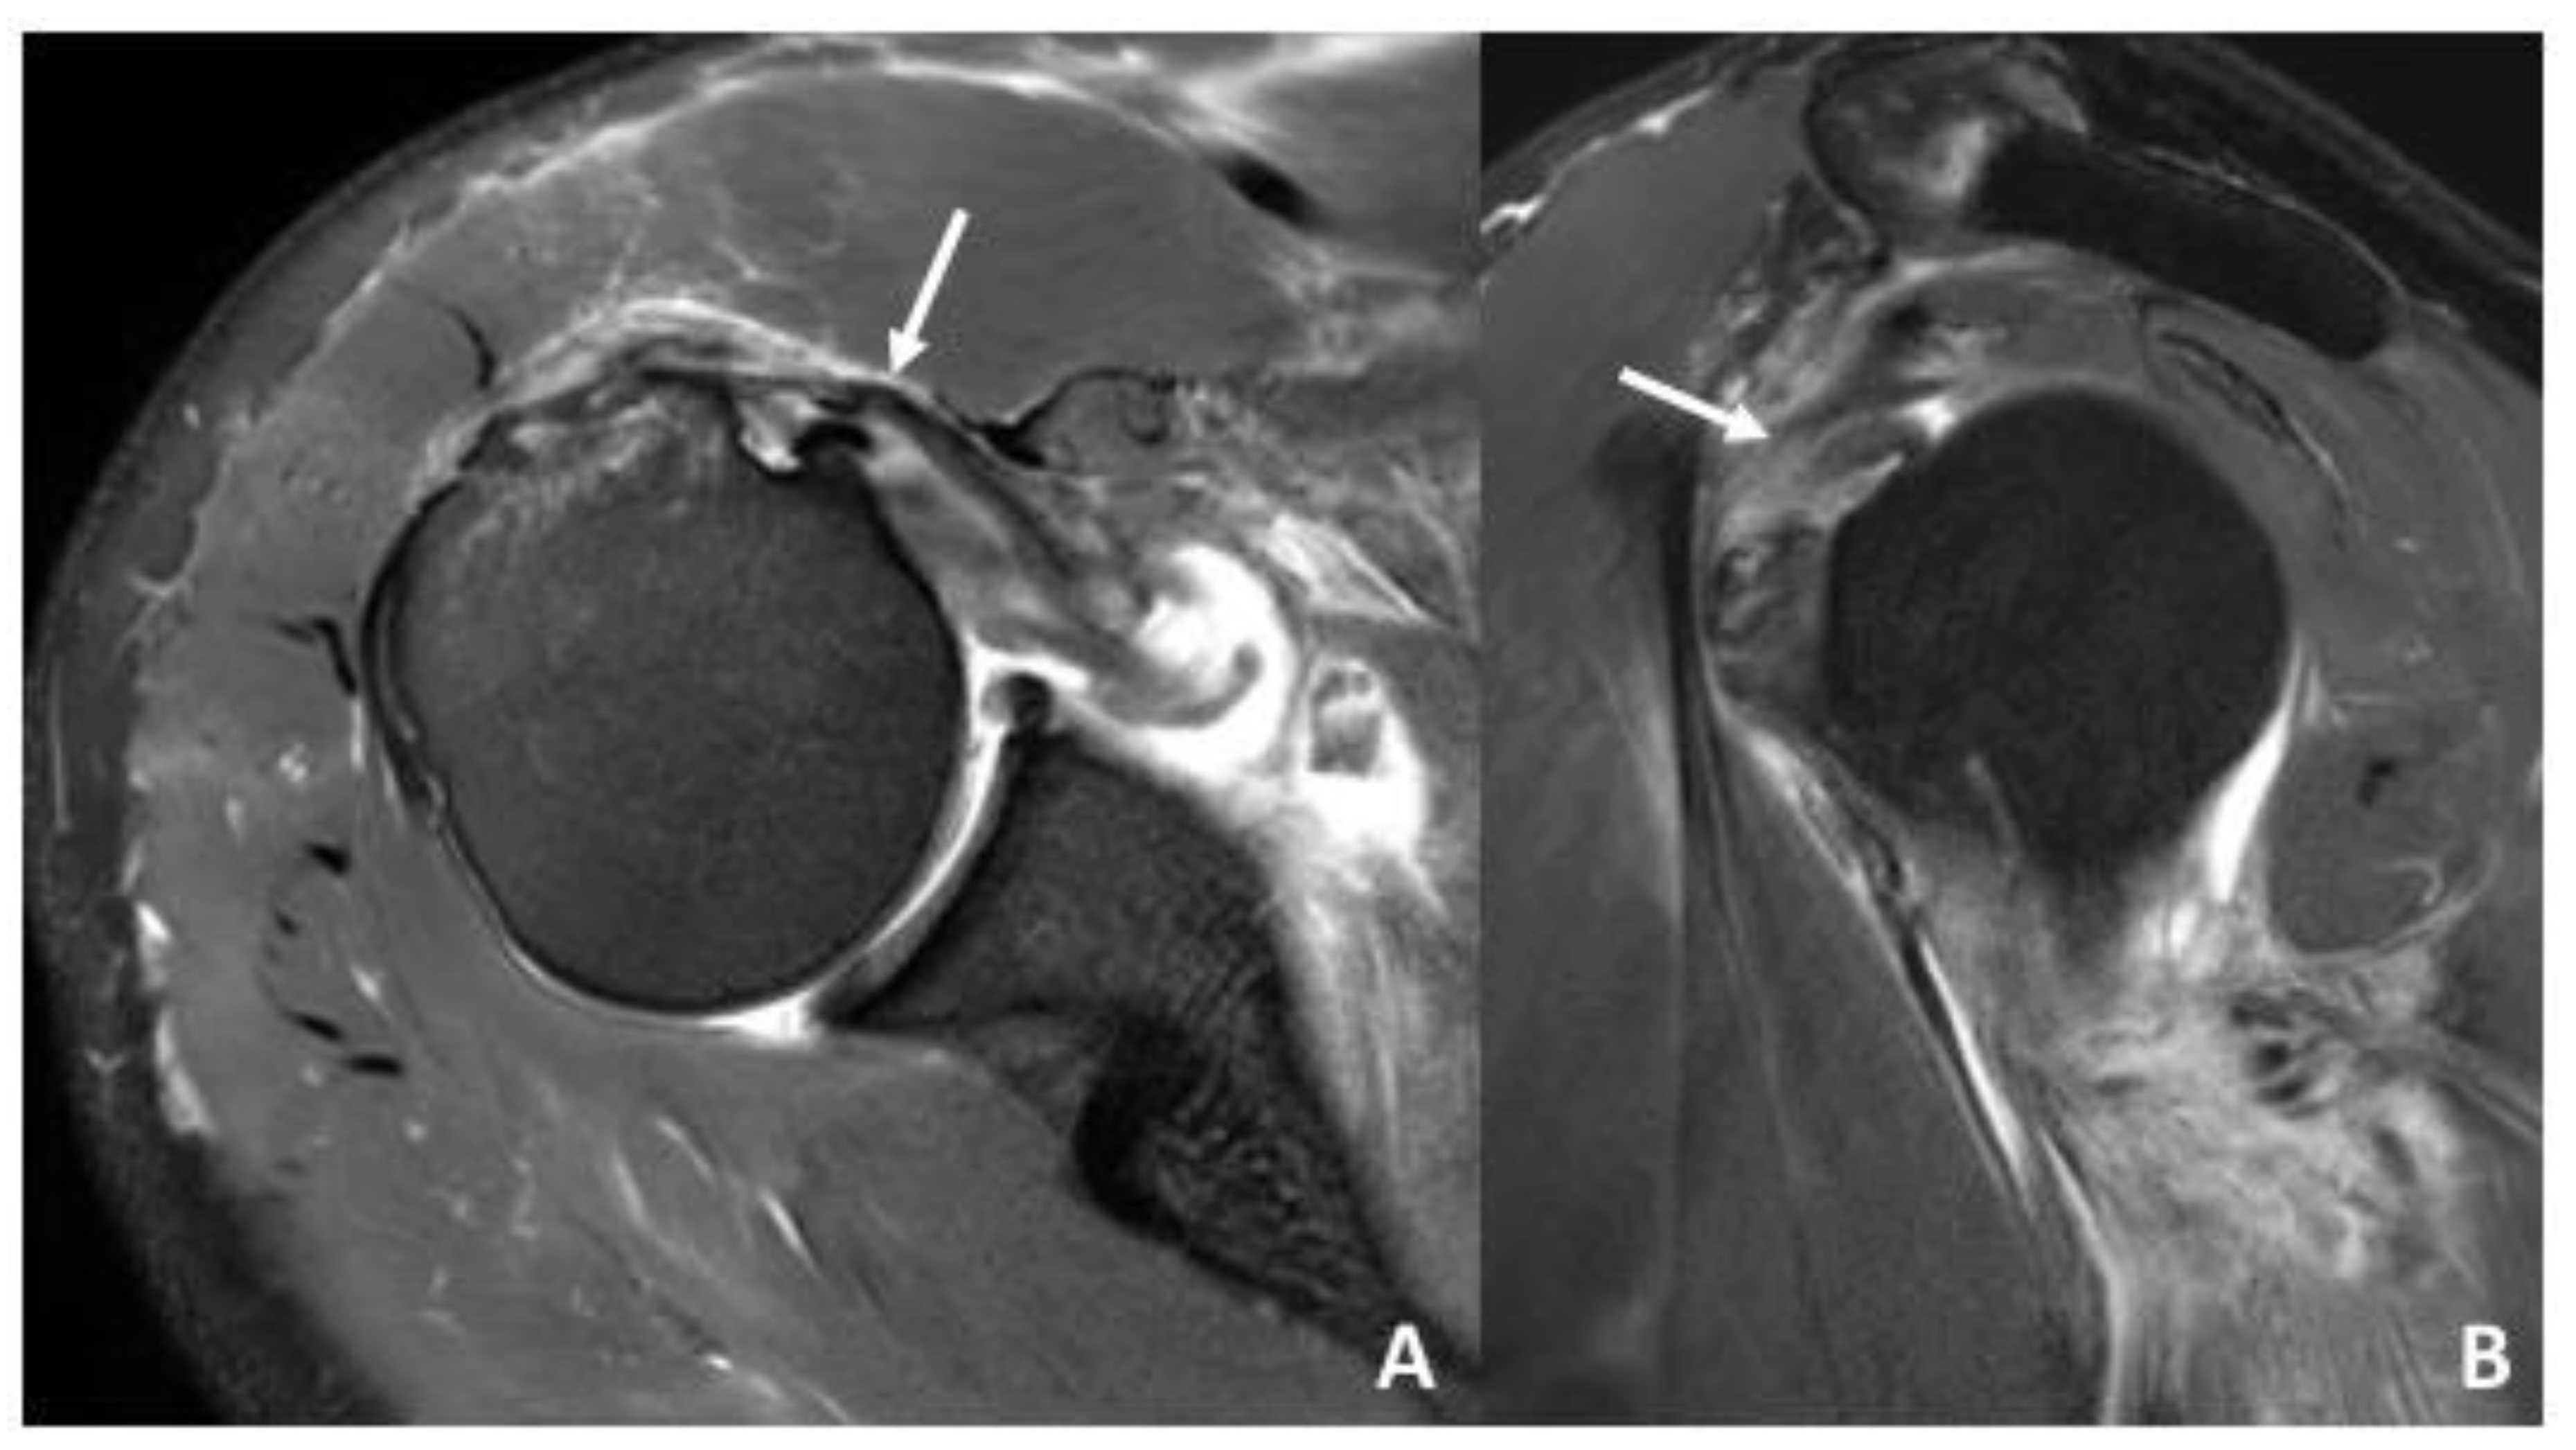

| Biceps pulley | Pulley Lesions graded according to Habermeyer et al. [8] | sGHLtear: 16 (48%) CHL tear: 12 (36%) sGHL and CHL tear: 11 (33%) |

| LHBT | Subluxation/dislocation of the LHBT | Subluxation: 4 (12%) Dislocation: 0 (0%) |

| Rotator cuff tendons | Tendinopathy including: subacromial impingement, rotator cuff tendinitis/tendinosis, calcific tendonitis. | No pathology: 10 (30%) Tendinopathy: 16 (48%) Partial or complete tear: 20 (61%) |